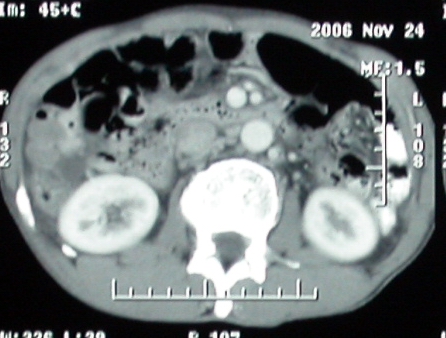

增强ct所见【动脉增强期】

门脉主干及肠系膜上静脉近端明显增粗,尤其前者呈等低混杂密度,增强后周围见轻度环形强化。明显占位效应。肝内外胆管见大量气体影。胆囊明显增大。

考虑:1、门脉栓塞; 2、肝内外胆管积气。

影像表现:胆囊扩张、肝内胆管不扩张,且见肝脏内树枝样气体影;十二指肠后方等密度占位,中心有不规则囊变区。增强实质部分轻度强化。下部腔静脉未强化------有栓子吗?

ct表现:1,胰腺钩突后方肿块,不均强化,中心密度低,钩突及门静脉前移。2:肝右后叶不均强化灶,突出肝表面,3:胆囊明显增大,肝内胆管及肝总管内积气。4:腹腔内少量积液。